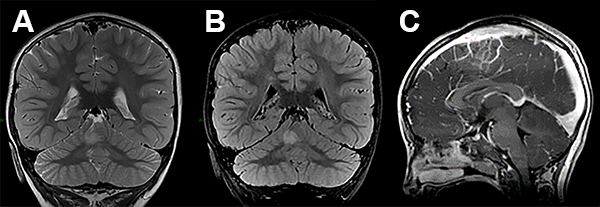

La RMN de encéfalo evidenció una lesión expansiva cerebelosa en contacto con el IV ventrículo y los pedúnculos cerebelosos superior y medio izquierdo, con leve efecto de masa que no realza con contraste (fig. 1).

Figura 1: Caso 1 imágenes prequirúrgicas.